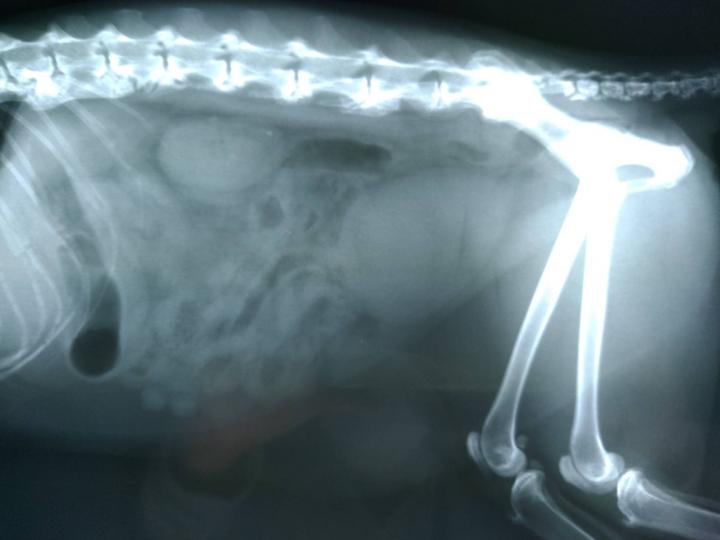

あれ?でも、お母さん。何で背骨のレントゲンばかりなの?骨軟骨異形成症候群だったら、足か尾だけだよね?

え?先生が「背骨にカルシウムが蓄積してる」って

あ、それは骨軟骨異形成じゃなくて、変形性脊髄症じゃないかな?

調べてみたらですね、変形性脊髄症は、何らかの原因で、体が背骨を補強しようとして、カルシウムが集まり、それが突起などの変形をして場合によっては痛みから歩行困難等になるらしいです。

直接、先生から聞いていないので解らないのですが、骨折の後もあったとか。